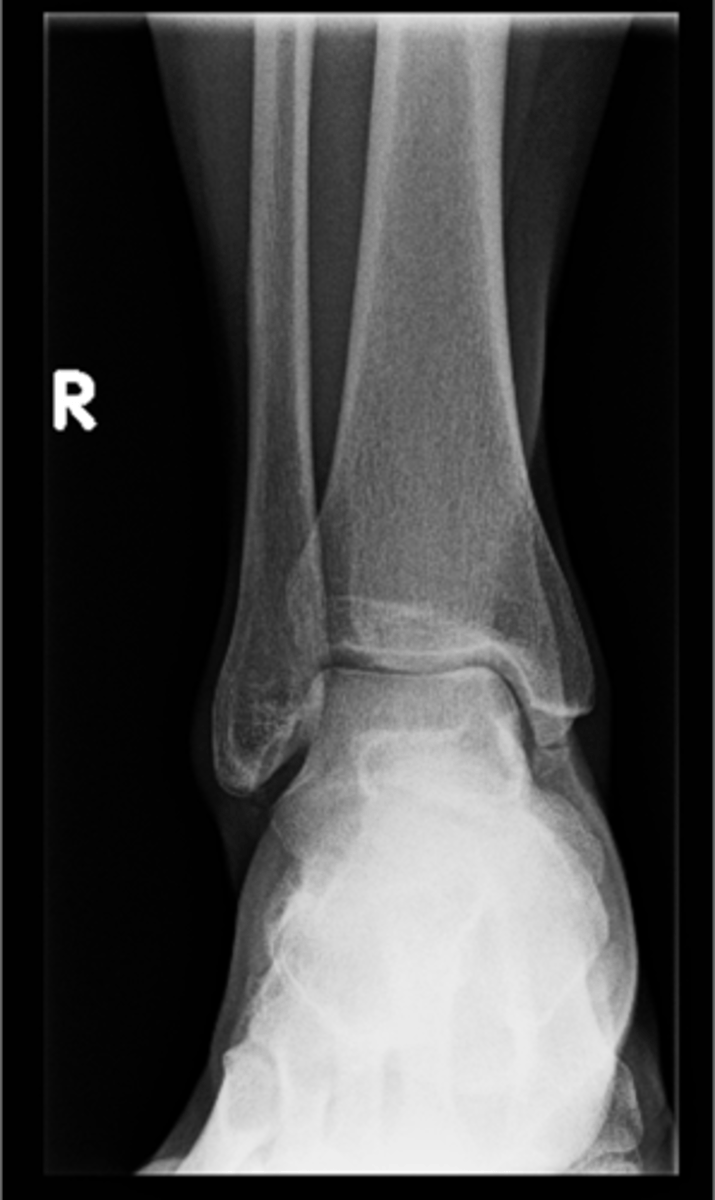

Right posterior superior iliac spine

ID 11

<p>ID 11</p>

12

New cards

Left femoral neck